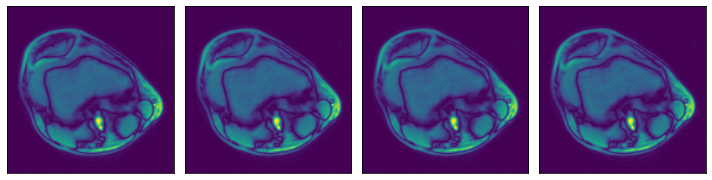

We can check that the data is equivalent in both representations:

[3]:

ser00001_2d = [

np.load(os.path.join(data_dir_2d, "SER00001", f"{i}.npy")) for i in range(4)

]

plot_batch(ser00001_2d)

../../../../_images/examples_general_data_loading_numpy_reader_pipeline_mode_6_0.png

[4]:

ser00001_3d = np.load(os.path.join(data_dir_3d, "SER00001.npy"))

plot_batch([ser00001_3d[0], ser00001_3d[1], ser00001_3d[2], ser00001_3d[3]])

../../../../_images/examples_general_data_loading_numpy_reader_pipeline_mode_7_0.png